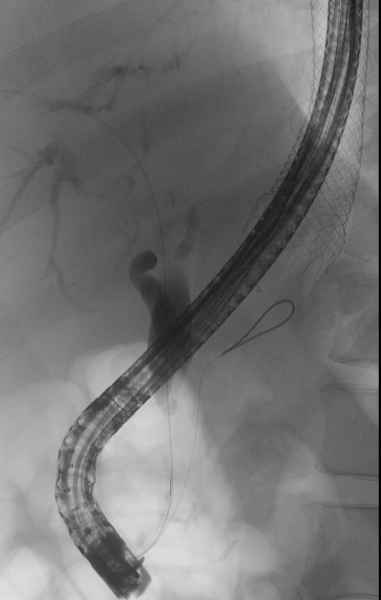

Gallstone ileus: A rare cause of bowel obstruction in a liver transplant patient

Fotografia